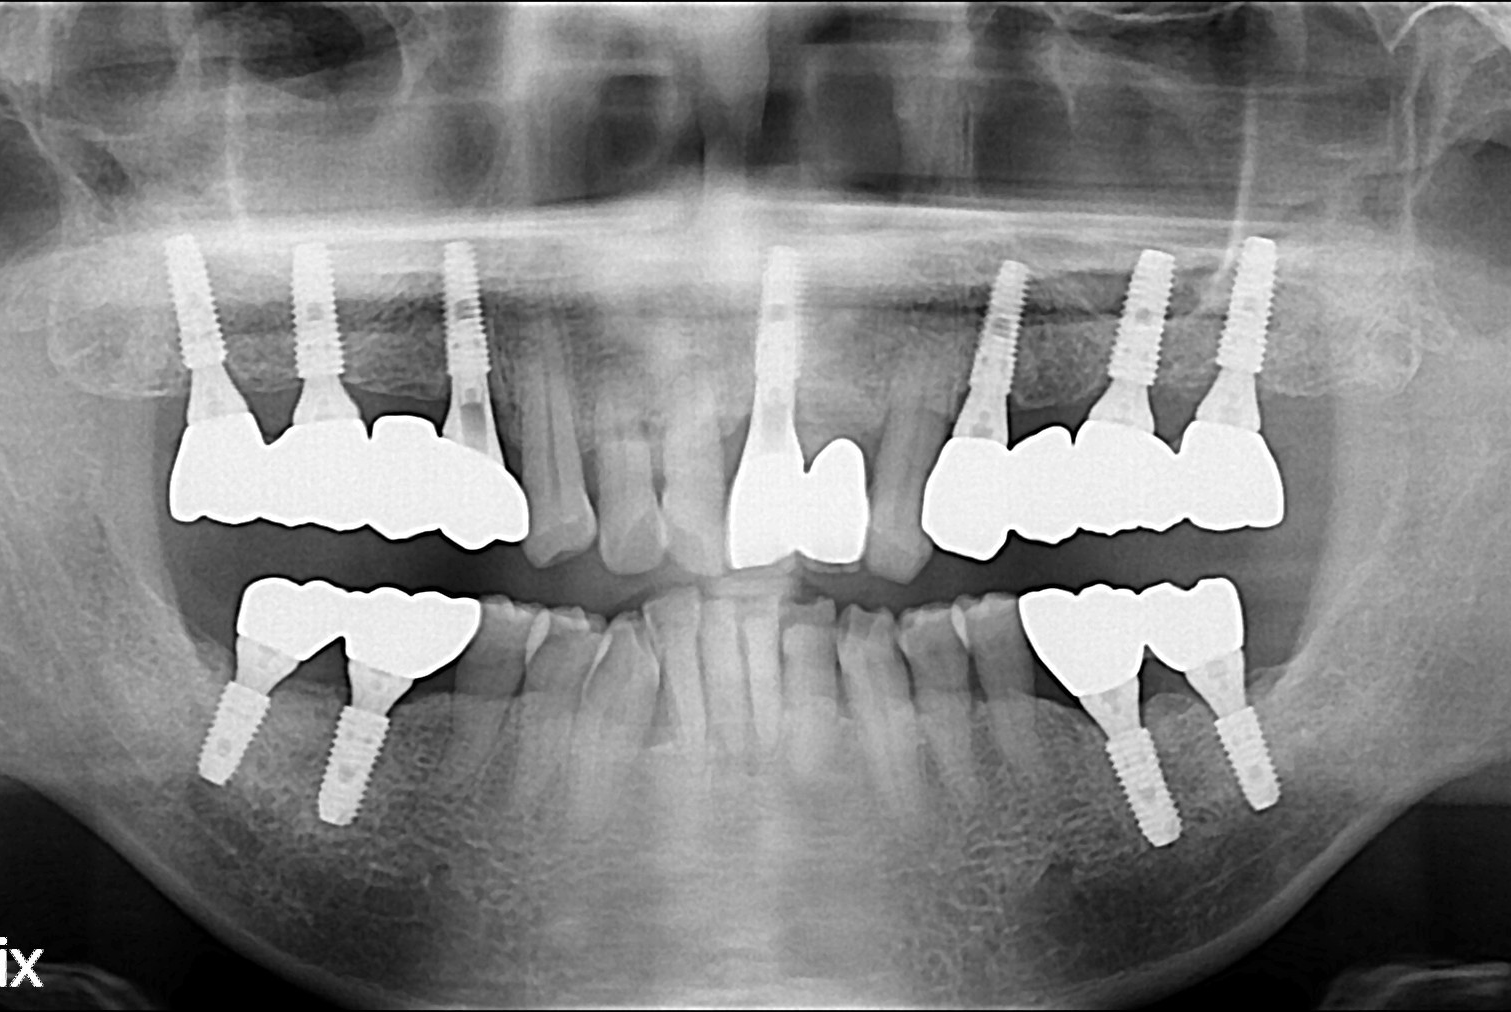

황채화 후.jpg

치료후 : 2019-07-18

세종치과는 많은 환자와 다양한 케이스를 바탕으로 항상 편안한 임플란트 수술을 제공하고자 노력하고,

오래동안 튼튼히 쓸 수 있는 임플란트 수술을 가장 큰 목표로 삼고 있습니다